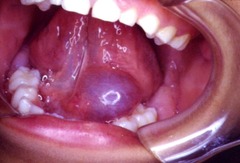

Bluish pink fluid filled nodule on lower lip caused by severance of the salivary gland a)Mucocele b)Pleomorphic adenoma c)epidemic parotitis (mumps) d)Ranula

Front

Mucocele

Back

Fluid filled nodule on the floor of the mouth, usually associated with sublingual gland. Known as the "mucocele of the floor of the mouth"

Ranula